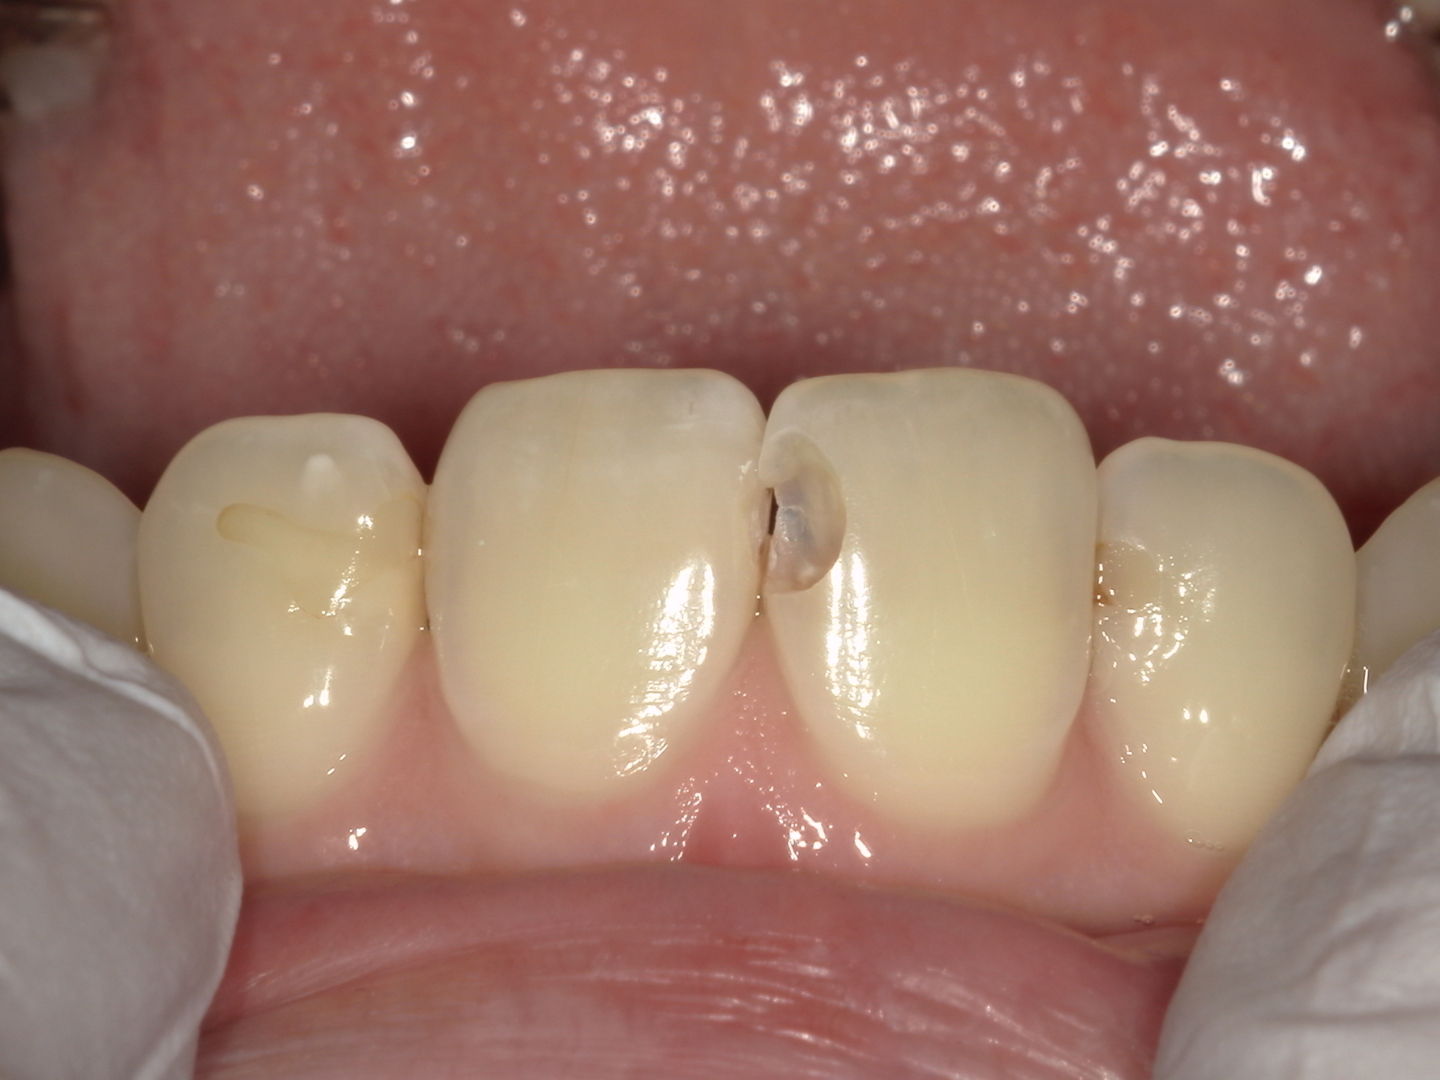

◆ 治療の途中経過(Before)

虫歯を全て取り除いた状態です。特に前歯部は、左右差や形の乱れが目立ちやすい部位です。詰め物が不適合の場合は、

-

見た目の違和感

食べ物が詰まりやすい

フロスが引っかかる

といった症状につながることがあります。